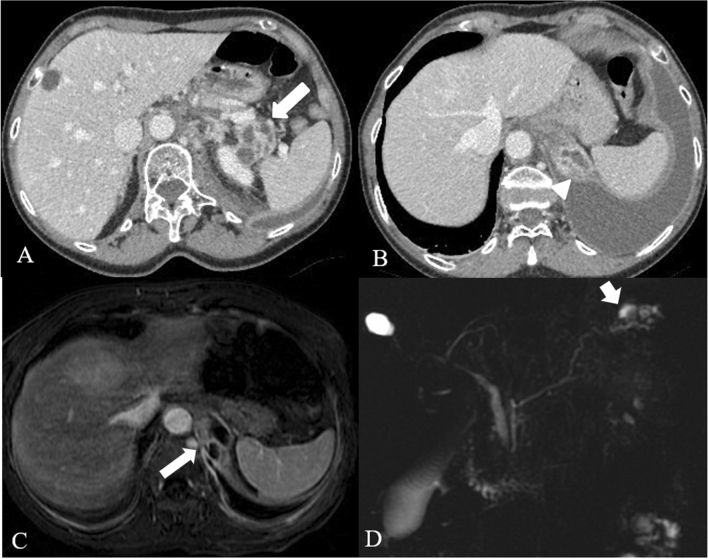

Apart from collections, other complications may occur, such as vascular complications. Splenic vein thrombosis represents the most common vascular complication in patients with AP. The release of pancreatic enzymes in AP results in erosion of local vasculature which may lead pseudoaneurysm malformation as well as spontaneous hemorrhage; the most common source of bleeding is the splenic artery, portal vein, and other peripancreatic vessels [27]. Necrosis of the central pancreas results in the disruption of the main pancreatic duct in 40% of cases, that can be confirmed with pancreatic MRI and MRCP (Magnetic Resonance Cholangiopancreatography) (Fig. 11). Other complications of necrotizing pancreatitis are pancreatic duct strictures (Fig. 2), which may develop secondary to inflammation or healing following successful drainage of necrotic collections [27].

Fig. 11.

Fistula with pleural cavity in a 66 years-old woman with acute necrotizing pancreatitis. Multiple encapsulated fluid collections in the tail of the pancreatic parenchyma (arrow in a), as for necrotic spots. These collections extend upt to the left hemidiaphragm with pleural fistula and pleural effusion (arrowhead in b). Axial (c) post contrast T1w MR images and MRCP (d) confirm the pleural fistula (arrows)